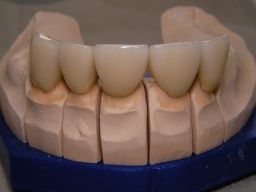

Links das Bild zeigt das Metallgerüst, das später mit Keramik verblendet wurde. Um eine einfache Mundhygiene ebenso wie eine hohe zahntechnische Präzsion zu erreichen, wurden risikobehaftete Verblockungen minimiert. Rechts die Ästhetikeinprobe bei entspannter Oberlippe.

Links Bilder des Oberkiefers, rechts des Unterkiefers. Die Arbeit wurde von dem Dentallabor "Heitmeyer Zahntechnik", Osnabrück, gefertigt. Dem Labor ist hier für die hervorragende Arbeit zu danken, dem Patienten für die Freigabe der Bilder!